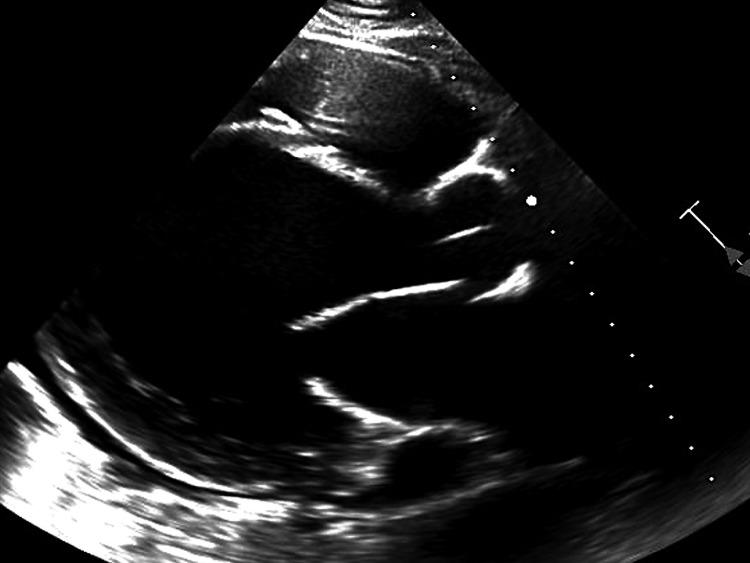

Myxedema coma is a rare and life-threatening consequence of severe hypothyroidism, often precipitated by physiologic stressors. While cardiac manifestations are common, they are typically reversible with prompt treatment. Here, we report a case of a 23-year-old male with untreated hypothyroidism who presented with myxedema coma-induced cardiomyopathy leading to refractory cardiogenic shock requiring veno-arterial extracorporeal membrane oxygenation (VA-ECMO) and, ultimately, orthotopic heart transplantation (OHT). Our case highlights a rare occurrence of refractory shock necessitating mechanical support as a bridge to a cardiac transplant. We emphasize early recognition, aggressive management, and a low threshold to escalate care to mitigate the high mortality associated with myxedema coma.